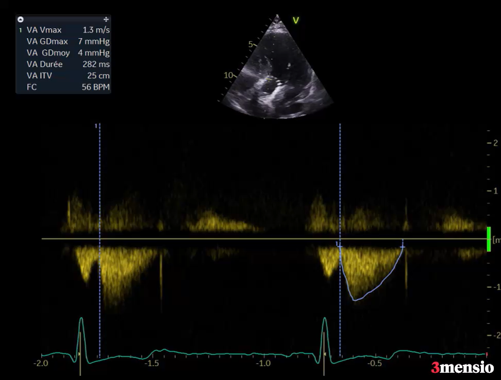

Figure 2

Coronarographie